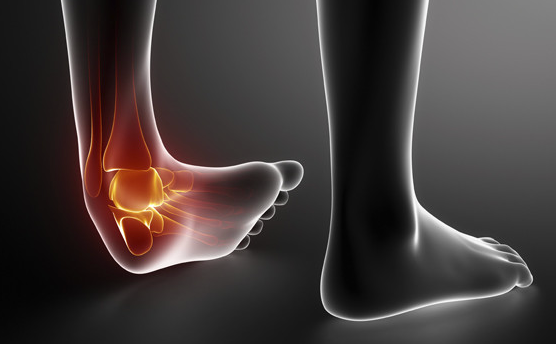

일반적인 증상

발목 통증의 일반적인 증상으로는 부종, 압통, 경직, 영향을 받은 발목의 체중 지탱 어려움 등이 있습니다. 구체적인 증상은 근본 원인에 따라 달라질 수 있습니다.